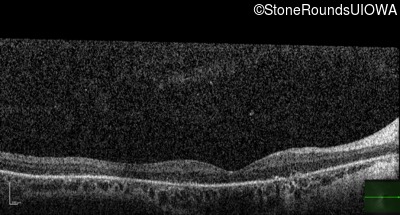

Optical Coherence Tomography - Left - 10/100 -1

Exemplar / OCT Stack